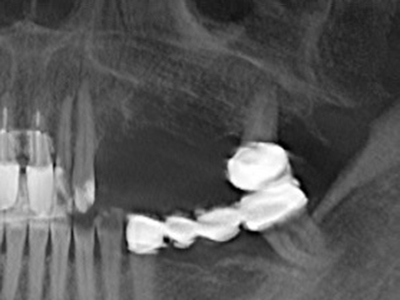

Indication: Preparations close to nerve tissue

As noted above, indications for piezo surgery can also be found in the field of conservative dental surgery. Special working tips simplify the exposure of root tips and make it easier to protect nerves and sinus mucous membranes, particularly in the lower premolar and upper posterior tooth regions. Angled diamond tips are used to precisely prepare the resection cavity for the retrograde root filler material for unsealed apical obturation. The ultrasonic technology means the tips can be very slender, which improves the view and the size of the access cavity. As a result, the application of ultrasonic surgery for this indication is one of the standard procedures for apical resection (Del Fabbro, Tsesis et al. 2010, Scarano, Artese et al. 2012).

Indication: Apical resection

When surgical procedures are performed on bone in the immediate vicinity of sensitive structures such as blood vessels or nerves, rotary instruments pose a significant risk of iatrogenic injury. Piezoelectric devices can be helpful for preparation of bone covers and removal of hard tissue close to nerves, particularly for exposure of nerves after iatrogenic injury but also during nerve lateralization for resective and reconstructive procedures or implant placement (Fig. 17-20). Light contact between the piezotip and the nerve does not generally result in damage but proceeding incautiously with saw-like motions or attachments where a residual bone substrate remains may cause temporary or even permanent nerve damage. However, the risk of damage is considered to be substantially lower than when using saws or milling instruments (Pereira, Gealh et al. 2014).